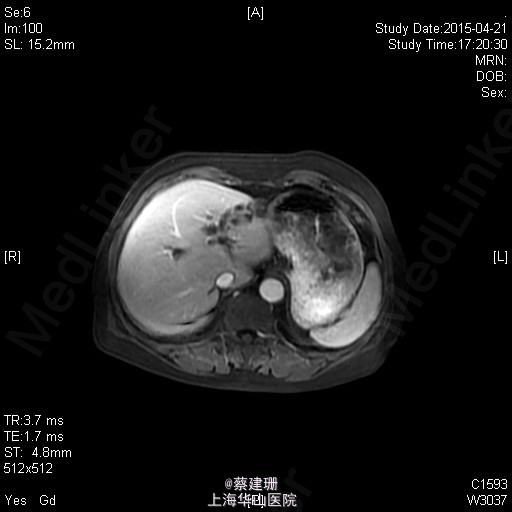

2015-4-21 肝脏MRI:肝左叶病灶;考虑胆管结石伴胆管扩张,胆管来源肿瘤待排,请结合临床。胆囊炎;双肾囊肿。 入院后完善术前准备,排除手术禁忌后,2015-4-22全麻下行腹腔镜下左半肝切除术。